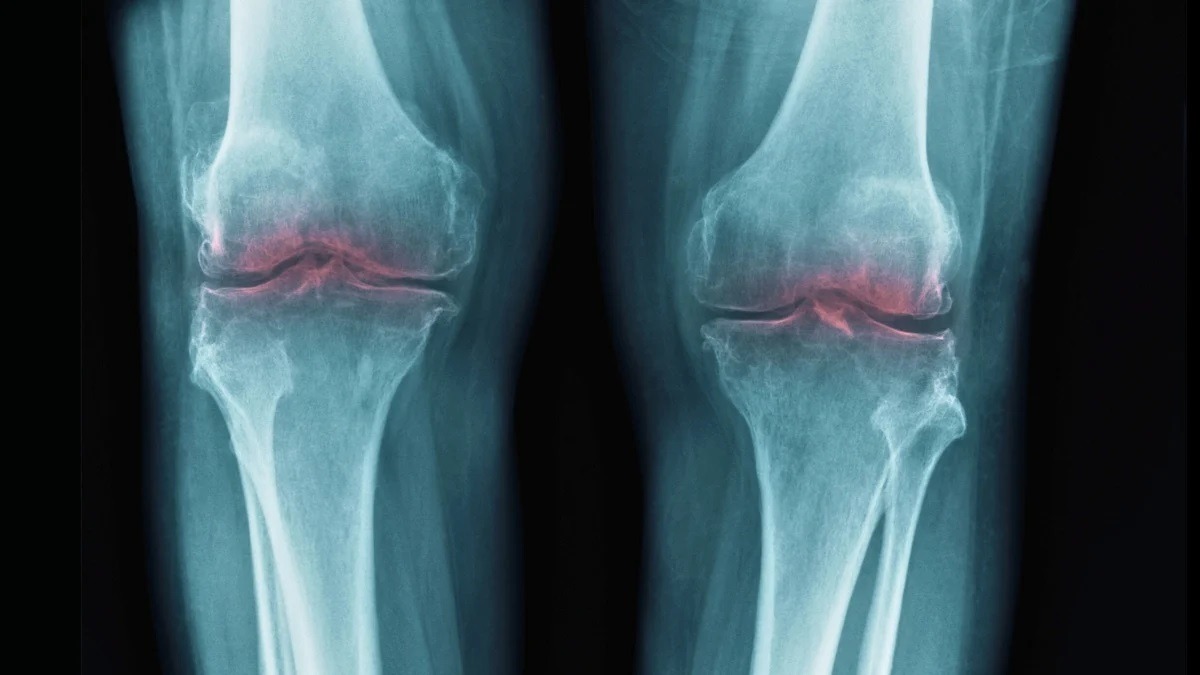

Каждый сустав в нашем теле — будь то колено, бедро или плечо — устроен как продуманный механизм. Концы костей покрыты суставным (артикулярным) хрящом — гладкой и упругой тканью, которая работает как амортизатор. Внутри суставной капсулы находится синовиальная жидкость — густая смазка, которая уменьшает трение между поверхностями и доставляет к хрящу питательные вещества.

Проблема в том, что хрящ плохо восстанавливается. У него нет собственного кровоснабжения, поэтому повреждения накапливаются. Причём скрытые повреждения коленей после 30 встречаются гораздо чаще, чем кажется, даже у людей без явной боли. С годами хрящевая ткань истончается, синовиальной жидкости становится меньше, а суставы начинают болеть и терять подвижность. Этот процесс и называется остеоартритом (или остеоартрозом — в русскоязычной медицине термины используются как синонимы).

По данным масштабного анализа Global Burden of Disease Study 2021, опубликованного в журнале The Lancet Rheumatology, остеоартритом страдает около 595 миллионов человек — это примерно 7,6% населения Земли. Чаще всего поражаются коленные, тазобедренные суставы и суставы позвоночника. Причём с 1990 года заболеваемость выросла более чем на 130%.